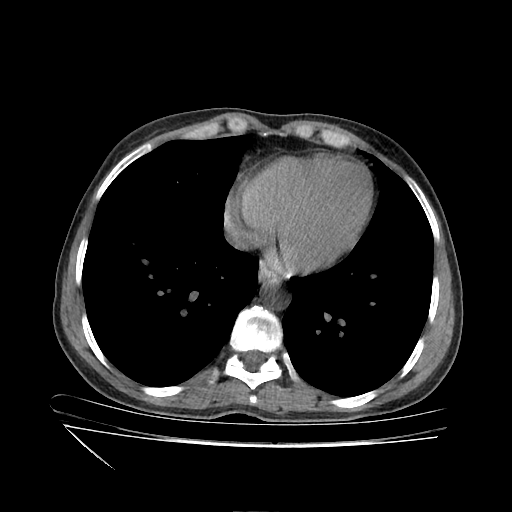

Image Grid

4×3 grid: Rows show different image types (Original NATIVE, Reconstructed NATIVE, Original VENOUS, Generated VENOUS), Columns show windowing techniques (No Window, Lung Window, Mediastinum Window)

Original VENOUS CT scan

No window - Raw intensity values

Original VENOUS CT scan

Lung window (WL -600, WW 1500 → Low −1350, High +150)

Windowing Parameters

- No Window: Raw intensity values without windowing

- Lung Window: WL -600, WW 1500 → Low −1350, High +150 (optimal for pulmonary structures)

- Mediastinum Window: WL 40, WW 400 → Low −160, High +240 (optimal for soft tissues)